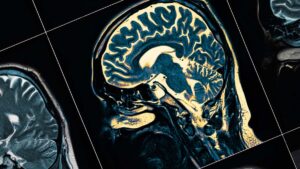

تصویربرداری و آزمایشهای عملکرد مغز

آزمایشهای تصویربرداری مغز میتوانند اطلاعاتی در مورد ساختار یا عملکرد مغز ارائه دهند. این آزمایشها ممکن است شامل MRI یا سیتیاسکن باشند که تصاویر دقیقی از مغز را نشان میدهند.

این تصاویر ممکن است تغییرات مغز را در نواحی تحت تأثیر بیماری هانتینگتون نشان دهند. البته شاید این تغییرات در اوایل دورهی بیماری ظاهر نشوند. همچنین این آزمایشها میتوانند برای رد سایر شرایطی نیز که ممکن است باعث ایجاد علائم مشابه بیماری هانتینگتون شوند، استفاده شوند.